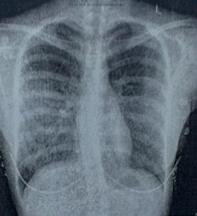

(图:魏先生强直治疗前状况)

(图:魏先生到院检查强直症状)